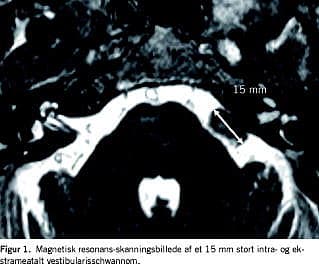

I henhold til international klassifikation [20 ] blev tumorerne kategoriseret enten som rent intrameatale eller som både intra- og ekstrameatale. Afhængig af den største ekstrameatale diameter blev tumorerne inddelt i følgende grupper efter størrelse: intrameatale 0 mm, små 1-10 mm, medium 11-20 mm, moderate 21-30 mm, store 31-40 mm og meget store tumorer med en ekstrameatal diameter større end 40 mm (Figur 1 ). Definitionen af signifikant vækst i gruppen af intrameatale tumorer var vækst til ekstrameatal udbredelse, i gruppen af intra- og ekstrameatale tumorer var vækst defineret som mindst 3 mm øgning af den største ekstrameatale diameter mellem den diagnostiske og den sidste CT/MR-skanning. I tilfælde af signifikant vækst blev patienten anbefalet at lade sig behandle enten med kirurgi eller strålebehandling.